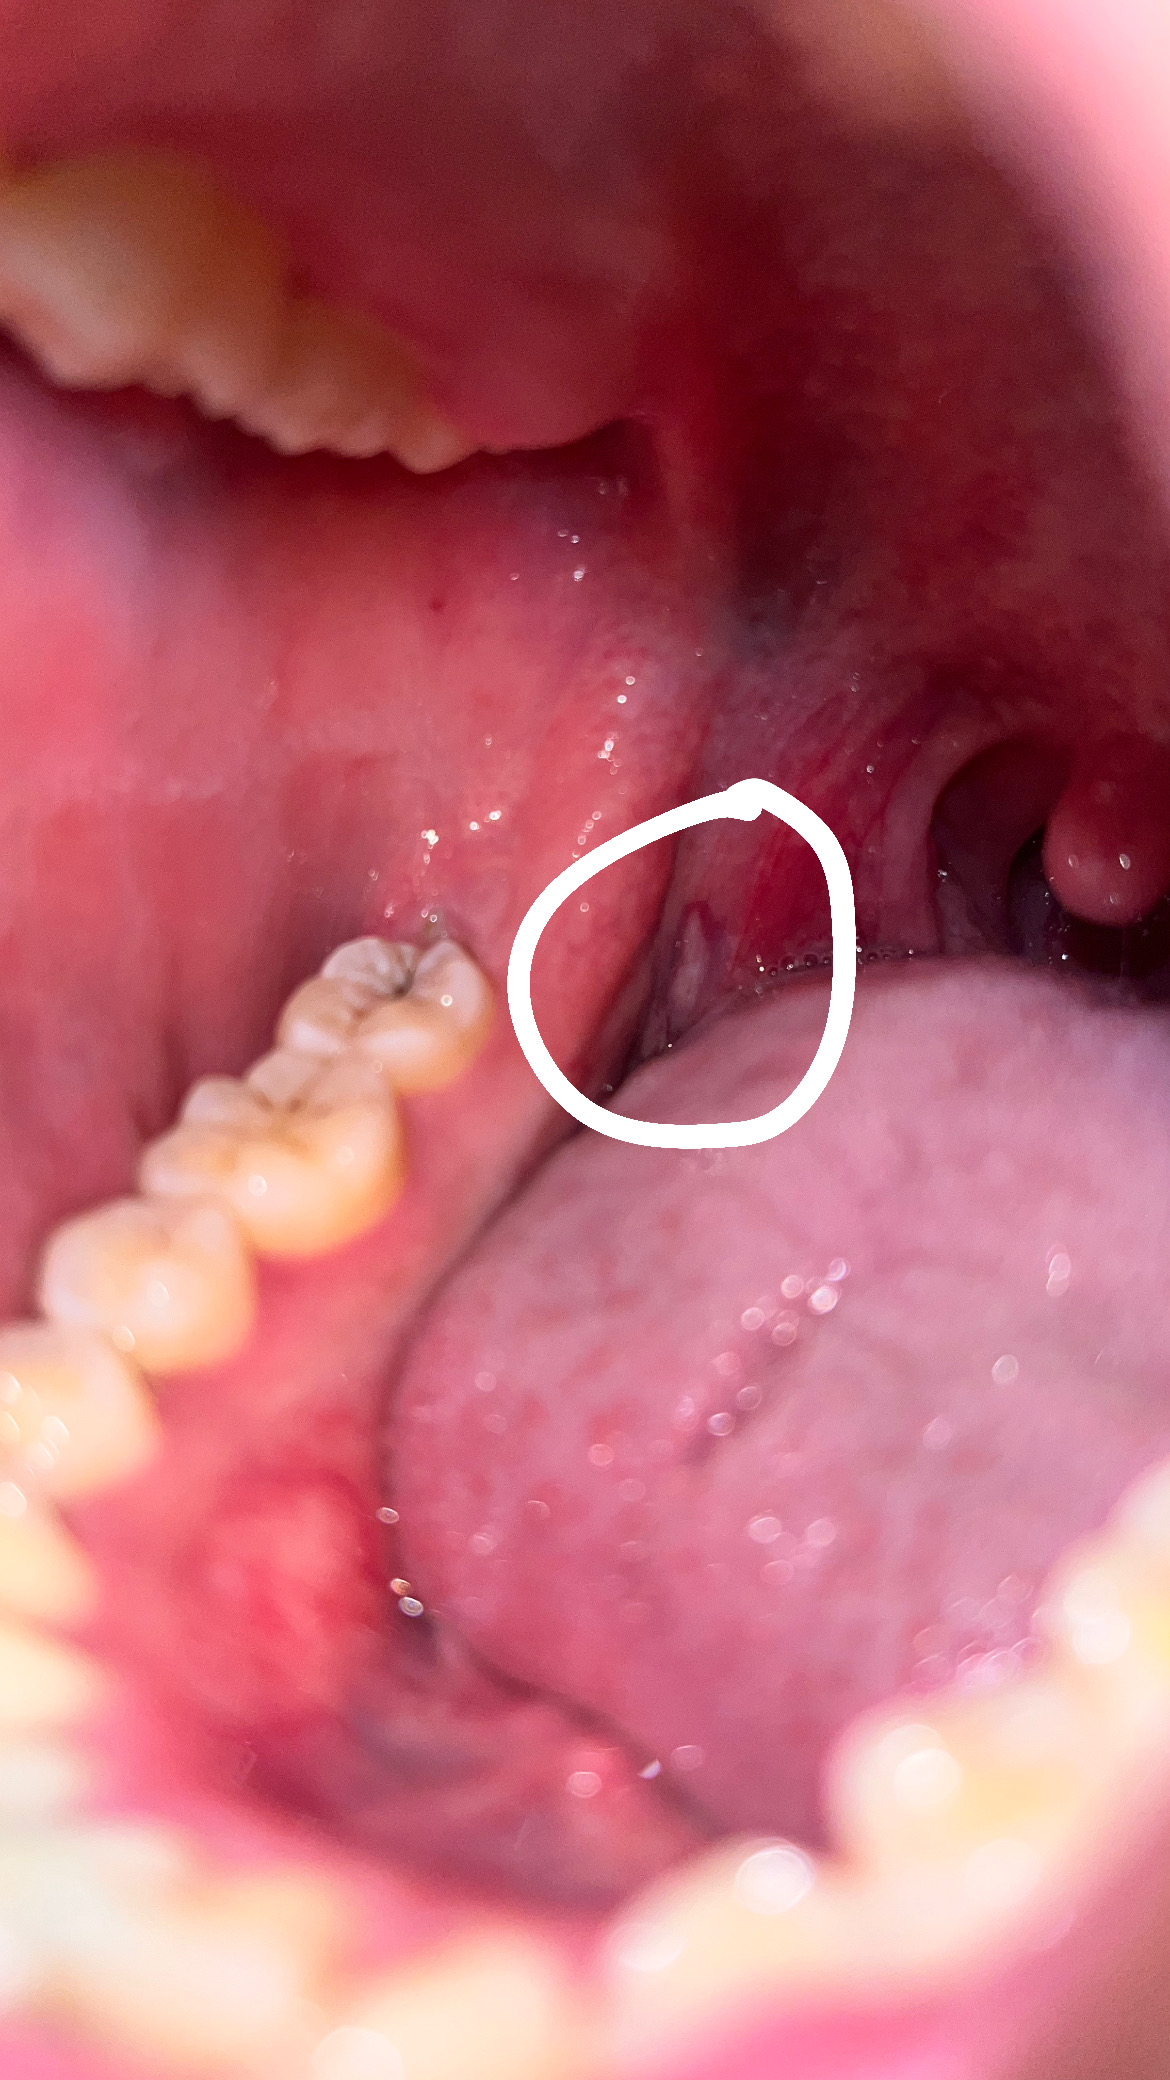

อยากทราบว่าสีขาวๆ คืออะไรหรอครับ และอันที่วงๆ ก่อนหน้านี้มีเจ็บคอเป็นๆ หายๆ บ่อย เคยเป็นกรดไหลย้อนนานแล้ว  กับภูมิแพ้ ผมสงสัยว่าสีขาวๆ คืออะไร ที่วง และกับอีกอันทอนซิลข้างขวาบวมหรือปล่าวครับ (แลบลิ้นเห็นชัดขึ้นอยู่ข้างขวา) กังวลมากครับ ขอบคุณมากครับถ้าตอบอธิบายให้หายกังวล

ลักษณะเหมือนกับแผลร้อนในน่าจะหายภายในสองอาทิตย์ครับ ส่วนต่อมทอนซิลไม่ผิดปกติสองข้างโตไม่เท่ากันได้ครับ ไม่ต้องกังวลครับ นอนหลับให้สบาย